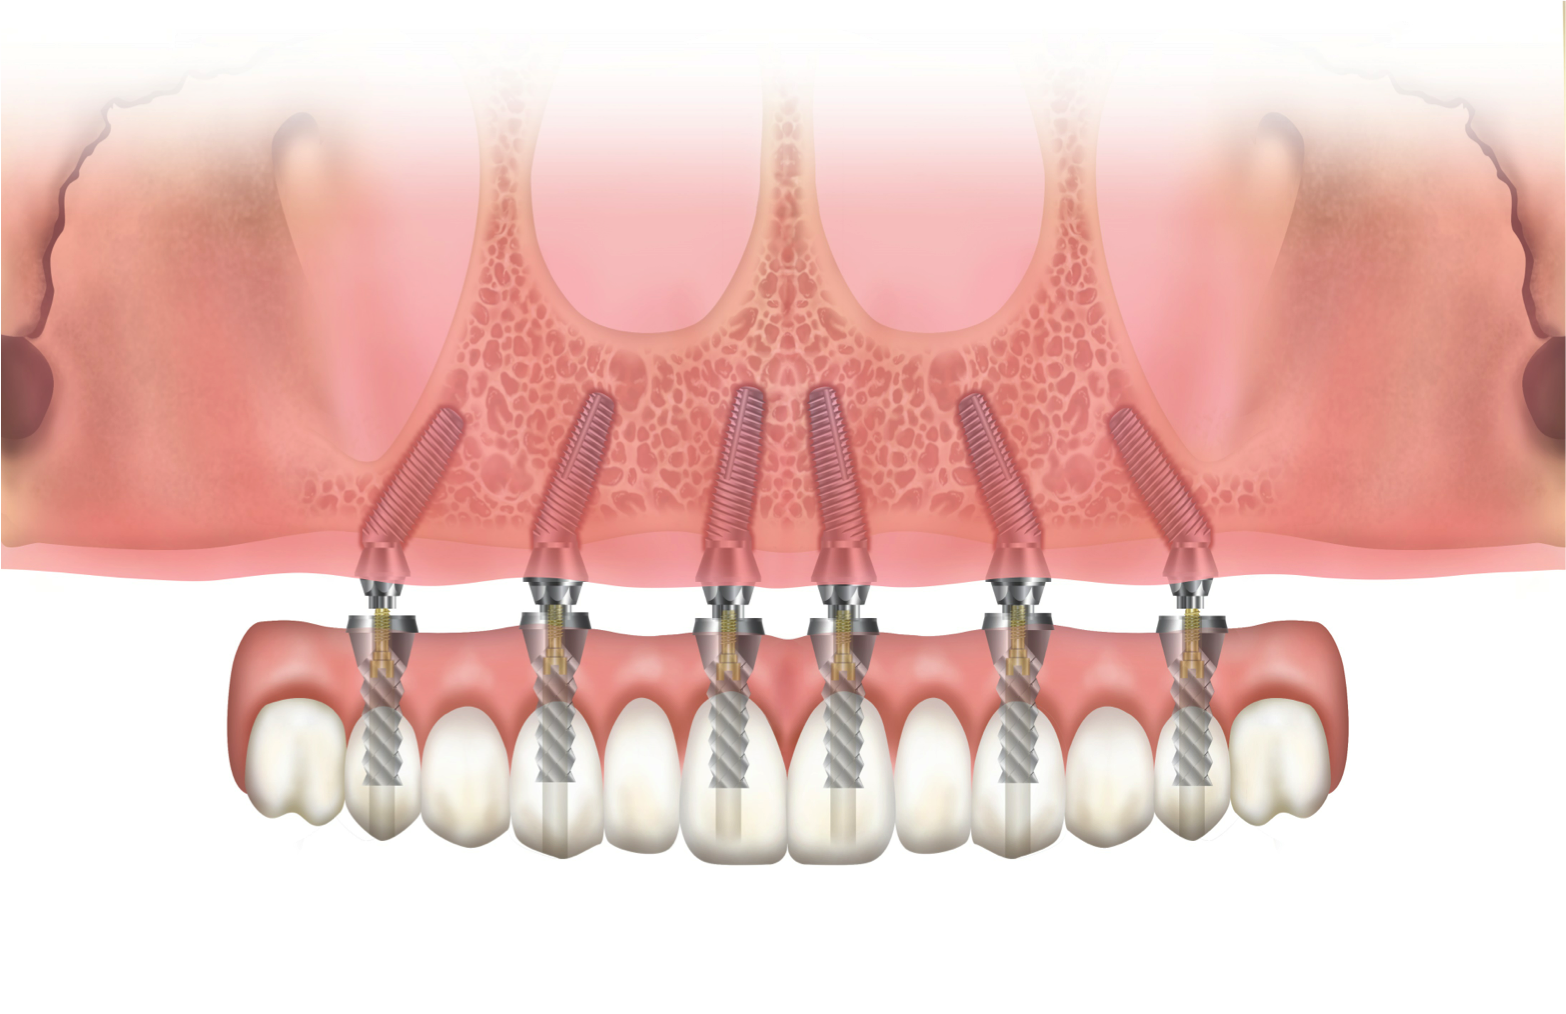

Fig 5. Dual-axial implant.

Figure 5

Fig 6. Dual-axial implant.

Figure 6

For surgical placement the dual-axis root form fixture is connected to an angle-correcting mount having a reciprocal inclination with the angulated platform of the implant enabling the fixture to be inserted in a straight axis (Figure 5 and Figure 6). An orientation dimple shows the rotational position of the implant in the bone.

This dual-axis system allows for desirable surgical placement within bone, avoiding anatomic structures such as described above and providing for the required prosthodontic needs of appropriate crown orientation and screw retention if needed. The use of this implant has been reported to yield predictable results,41-43 including a net buccal bone gain over time.44

The subcrestal angle-corrected, dual-axial implant has advanced the treatment of the anterior maxilla by reducing the need for grafting procedures and facilitating immediate loading. Good primary stability is achieved because the threads engage the palatal triangle of bone while avoiding the buccal plate. Figure 7 illustrates the advantages of a dual-axial implant over a uniaxial implant, which would require grafting to avoid apical perforation.45 The dual-axis implant allows for maintenance of the recommended 1.5 mm to 2 mm dimension between the buccal plate and the fixture.46

A distinction must be made between the tilting of straight implants with supracrestal angle correction by way of angulated abutments and implants with subcrestal angular correction within the neck of the fixture (Figure 2). The first angulated implant was the zygomatic implant, developed by Brånemark and placed in 1991; it was designed with angular correction within the head of the implant.36 This allowed for screw retention of prostheses supported by severely tilted implants to avoid the maxillary sinus and engage the bone of the zygoma. The use of this implant has also been described extensively for the resorbed and compromised maxilla in oncology and trauma.37,38

Development of a Root Form Dual-axis Implant

Howes et al40 described the research and development of an implant with 12-degree subcrestal angular correction, originally designed to overcome the anatomic constraints of the anterior maxilla for screw retention. In this unpublished study, the authors recognized the conflict between the surgical and restorative objectives in ISPs in the anterior maxilla. The morphology of the anterior maxilla was analyzed on lateral cephalometric radiographs of 30 class I to III maxillae. In addition, the differences between the axes of the crowns and roots of 30 anterior teeth were assessed, including canines and lateral and central incisors. The root–crown offset ranged from 8 to 12 degrees (Figure 3), and the angle between the buccal plate and ideal screw axis ranged from 25.6 to 30 degrees (Figure 4). The resultant fixture design had a 12-degree angular offset between implant body and prosthetic platform, with a 0.6-mm body thread pitch to minimize apical travel per rotation. This implant is able to accommodate these angulation constraints due to the combined taper and head angulation.

Finite element studies simulating 22-degree off-axis loading of implants positioned in the anterior maxilla showed strains developed in the dual-axis implant were well below the 483 MPa yield strength of grade 4 titanium. In contrast, the simulation showed that the uniaxial implant would suffer strains well above this threshold.40